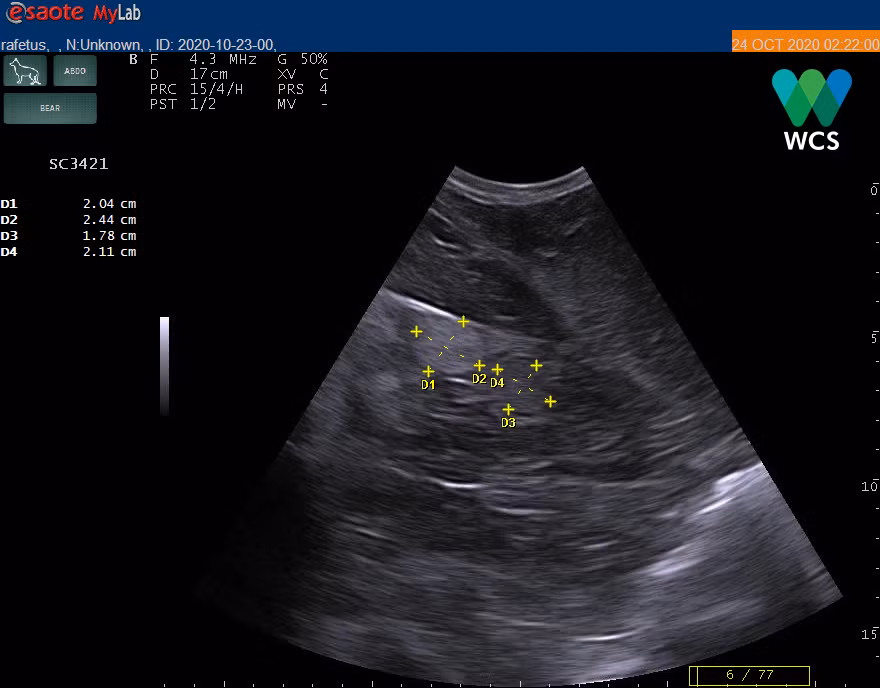

| Máy siêu âm soi được nang trứng của rùa, khẳng định đây là cá thể rùa cái. Nguồn ảnh: WCS Việt Nam |

Kết quả phân tích gene đã khẳng định cá thể rùa này 99,99% là rùa Hoàn Kiếm (Rafetus swinhoei). Giám định động vật được thực hiện bởi Viện sinh thái và Tài nguyên sinh vật, Viện Hàn lâm Khoa học và Công nghệ Việt Nam và phân tích gene độc lập của Phòng Tài nguyên Thiên nhiên và Bảo tồn, Viện Tài nguyên môi trường thuộc Đại học Quốc gia Hà Nội.